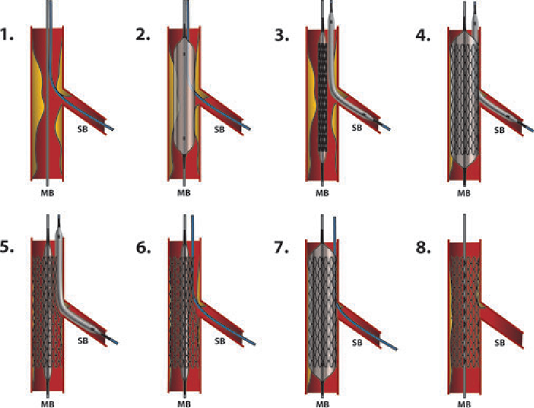

Phân tích Cath Report

1. Các hình ảnh của chụp mạch vành ở các động mạch khác nhau. Chụp mạch vành định nghĩa là hình ảnh XQ của mạch vành sau tiêm cản quang có iod [1]. Thủ thuật này là 1 phần của đặt catheter tim cũng có thể bao gồm đánh giá huyết động và hình ảnh các buồng tim khác (thường là thất trái). Chụp mạch vành tiến hành ở cả động mạch vành và trái, sử dụng catheter chuyên dụng, hình ảnh thu được ở các góc khác nhau để đánh giá giải phẫu mạch vành. Figures 71.1 và 71.2 giải phẫu mạch vành trái. Figure 71.1 là tư thế chụp chếch chân giúp đánh giá tốt nhất nhánh mũ và các nhánh của nó (mũi tên). Figure 71.2 là tư thế chếch đầu đánh giá tốt nhất nhánh LAD và các nhánh của nó (mũi tên). Figure 71.3 hình ảnh nhánh động mạch vành phải.

2. Có 2 động mạch thượng tâm mạc lớn: nhánh chính trái và nhánh vành phải bắt nguồn từ xoang trái và phải của xoang Valsalva ở đáy của đoạn lên động mạch chủ [2]. Động mạch chính trái chia làm nhánh xuống trước trái chính (LAD) và nhánh mũ trái (LCX). Trong 1 số trường hợp, nhánh chính trái còn chia thêm nhánh thứ 3 là nhánh trung gian. nhánh LAD và LCX chia thành nhánh xiên và nhánh bờ tù. Tuần hoàn vành nguồn gốc từ động mạch xuống sau (PDA) cấp máu cho phần sau của vách liên thất. PDA từ nhánh vành phải ở 70% bệnh nhân và nhánh mũ trái ở 15% bệnh nhân. Các trường hợp còn lại xuất phát từ cả nhánh phải và nhánh mũ [3].

Danh pháp của các đoạn khác nhau trên hệ mạch vành được mô tả bởi tổ chức Bypass Angioplasty Revascularization Investigation (BARI), và nằm ngoài phạm vi chương này [4]. Table 71.1 tóm tắt các nhánh chính của động mạch vành

3. Chỉ định chính đặt thông tim ở người lớn là xác định giải phẫu mạch vành và mức độ hẹp của mạch vành. Thủ thuật có thể theo chương trình hoặc cấp cứu [5]. Table 71.2 tóm tắt chỉ định chính của chụp mạch vành. Không có chống chỉ định tuyệt đối với đặt thông tim. Table 71.3 tóm tắt các chống chỉ định tương đối

4. Đặt catheter tim tương đối an toàn. Tuy nhiên, có 1 số biến chứng có thể xảy ra và bệnh nhân cần được trao đổi kỹ về chúng trước khi tiến hành thủ thuật xâm lấn. các biến chứng chính [5, 6] được tóm tắt trong bảng Table 71.4.

Table 71.1 nhánh chính của động mạch vành (hệ thống mạch bên phải)

Table 71.2 chỉ định thông tim

5. Sự cân bằng và nhu cầu cung – cầu oxy rất phức tạp và bị ảnh hưởng bởi nhiều yếu tố. các yếu tố quyết định nhu cầu oxy gồm tần số tim, co bóp cơ tim, tiền tải (thể tích hoặc áp lực cuối tâm trương), hậu tải (kháng trở mạch máu) và khối lượng cơ. Các yếu tố chính quyết định cung cấp oxy cơ tim gồm lưu lượng máu vành hoặc nồng độ oxy máu động mạch [7]. Lưu lượng tưới máu vành tỷ lệ thuận với áp lực tưới máu vành (áp lực động mạch chủ thì tâm trương—áp lwujc thất trái cuối tâm trương) và tỷ lệ nghịch với sức cản vi mạch (áp lực thành thất trái). Nếu nhu cầu vượt quá khả năng cung cấp, thiếu máu cục bộ cơ tim sẽ gây những ảnh hưởng xấu

6. Hẹp đáng kể động mạch vành đinh nghĩa là hẹp khi chụp vành ≥ 70% ở động mạch thượng tâm mạc lớn. khi chụp hẹp ≥ 50%

Table 71.3 chống chỉ định đặt thông tim

Table 71.4 tỷ lệ biến chứng khi đặt thông tim

8. Biến chứng liên quan

(a) Giả phình (0.5–9%)

(b) Rò động – tĩnh mạch (0.2–2%)

(c) Tắc động mạch (0.8%)

(d) Xuất huyết (tụ máu (5–23%); xuất huyết sau phúc mạc (0.1%))

(e) Nhiễm khuẩn (0.1%)

nhánh động mạch chính trái. Trong nhiều trường hợp, chúng không hẹp tới mức không thấy hẹp đáng kể và cần phải dùng test thăm dò thêm. Có nhiều cách để đánh giá mức độ hẹp như phân suất dự trữ lưu lượng mạch vành (FFR) và siêu âm nội mạch (IVUS). FFR định nghĩa là dòng máu tối đa tới cơ tim trong trường hợp có hẹp mạch vành, chia cho dòng máu tối đa ở mạch vành bình thường ở cùng khu vực phân bố [8]. ≤ 0.80 cho thấy có hẹp đáng kể và có khả năng gây thiếu máu cục bộ, sẽ có lợi khi can thiệp mạch [9]. IVUS có thể dùng để đánh giá hình ảnh động mạch vành và đánh giá hẹp tốt hơn. Diện tích dưới 4.0 mm2 (giá trị này thay đổi tùy nghiên cứu) ở động mạch thượng tâm mạc hoặc 6.0 mm2 ở nhánh trái chính cân nhắc có hẹp đáng kể [10].

7. khi kết thúc thông tim, cần có báo cáo hoàn chỉnh để có thể có thông tin cho can thiệp và tham khảo sau này. Table 71.5 tóm tắt các thông tin cần có trong báo cáo

Table 71.5 thành phần trong báo cáo